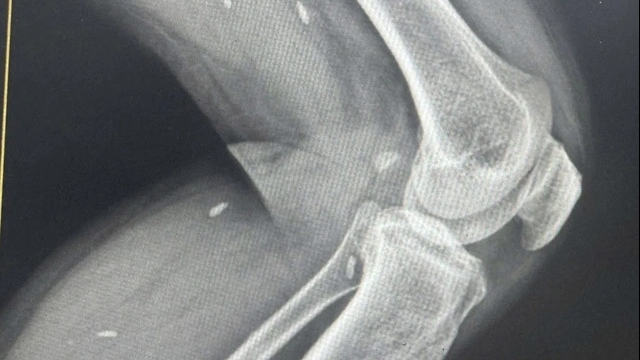

Bệnh nhân ngay lập tức được đưa đi cấp cứu tại Bệnh viện Đa khoa tỉnh và đặt ống nội khí quản cấp cứu, an thần, thở máy, chụp cắt lớp vi tính sọ não. Sau đó, bệnh nhân được chuyển lên Bệnh viện Trung ương Quân đội 108 trong tình trạng ý thức đang duy trì an thần và thở máy.

Tại Khoa Hồi sức Thần kinh (Bệnh viện Trung ương Quân đội 108), các bác sĩ tiến hành điều trị hồi sức cơ bản tích cực cho bệnh nhân như: An thần, giảm đau, thở máy, kiểm soát huyết áp, chống động kinh.

Đồng thời, các bác sĩ tầm soát các nguyên nhân gây ra trạng thái động kinh như xét nghiệm máu, chụp cắt lớp vi tính sọ não, chọc dịch ống sống thắt lưng xét nghiệm dịch não tủy. Bệnh nhân được xác định nguyên nhân gây ra trạng thái động kinh là do ngộ độc thuốc bảo vệ thực vật.